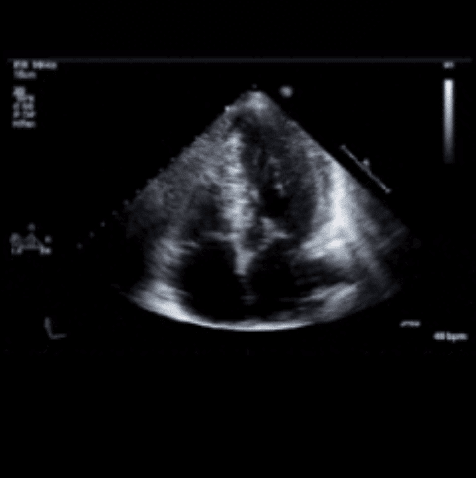

Viz HCM

Detection of Hypertrophic Cardiomyopathy on Electrocardiogram Using Artificial Intelligence

The device identified HCM based on a 12-lead electrocardiogram with good performance. Coupled with clinical expertise, it has the potential...